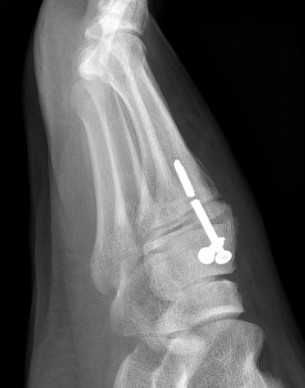

5. Dorsal subluxation of the metatarsals

Dorsal subluxation of the metatarsal